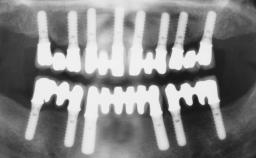

Immediate Loading of Six Implants in the Mandible and Six Implants in the Maxilla and Final Restoration with Full-Arch CAD/CAM Metal Framework FDPs Involving Digital Planning and Guided Surgery

Immediate loading of dental implants is increasingly popular with clinicians and patients. The idea of delivering a restoration directly after implant insertion,combined with a less invasive procedure (flapless protocol), has made treatment protocols involving dental implants more accessible to dentists and patients. However,immediate-loading concepts require sophisticated and exact planning. To facilitate this, conventional panoramic tomographs and periapical radiographs are often taken with the patient wearing a radiographic template simulating the preoperative prosthetic design. However, these radiographs do not provide all the necessary information. In addition, some protocols call for conventional surgical templates fabricated on the diagnostic cast. These will inform the bone drilling points and drill angles, but do not reference the underlying anatomical structures or provide exact 3-D guidance.